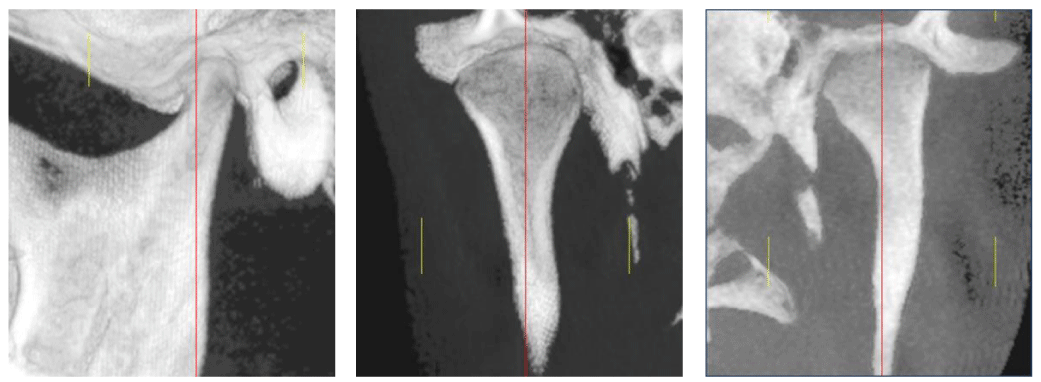

TMJ pre-orthodontic, cephalometric and routine tests were indicated. Patients were informed about procedures and consented to the present study. In the differential diagnosis of temporomandibular joint pathology, age and sex were not significant for this investigation. A total of 38 joints were evaluated as independent units [Figure 3a,b,c].

Figure 3a-c: CBCT images analyzed with Dolphin Imaging 11.7 Software. Sagittal cut 1 - a, coronal cuts1 - b and 1 - c

Figure 4a-c: Hard structures. Sagittal view a. Coronal views b - c

Taking as a reference the major condylar axis in a horizontal plane, a sagittal cut was reconstructed, which indicates the following sections: external auditory meatus, articular eminence, mandibular condyle, fossa and 2/3 of the mandibular ramus (Figure 4a). Acoronal cut shows the mandibular condyle, neck, fossa, and 2/3 of the mandibular ramus (Figure 4 b-c).

Figure 7a,b: Coronal direction analysis of the condyle. Note the difference in the degree of internal rotation in articulation b, compared to articulation c.